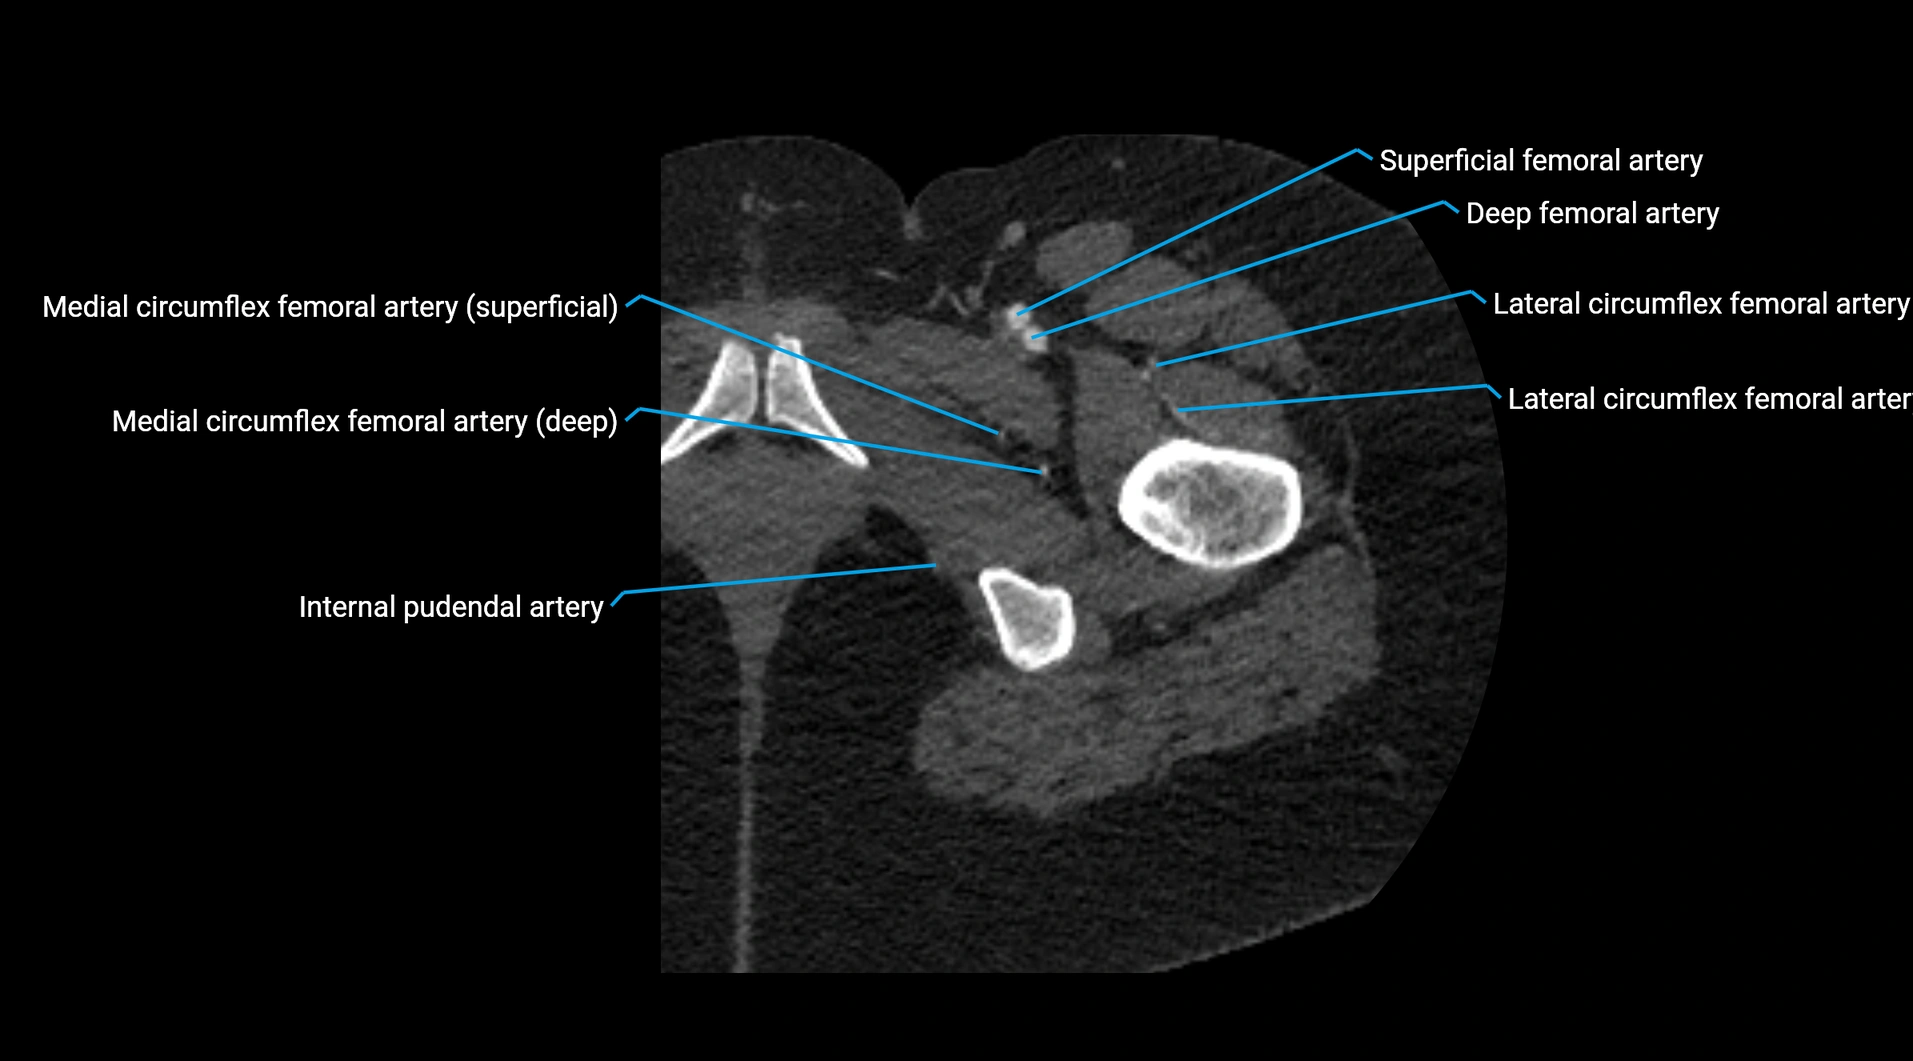

Contrast-enhanced CT (CTA):

• Gold standard for abdominal aortic imaging

• Provides excellent detail of lumen, wall, aneurysm, thrombus, and branch vessels

• Multiplanar and 3D reconstructions help in aneurysm measurement, stent graft planning, and dissection evaluation

• Detects acute rupture, traumatic injury, or occlusion with high sensitivity